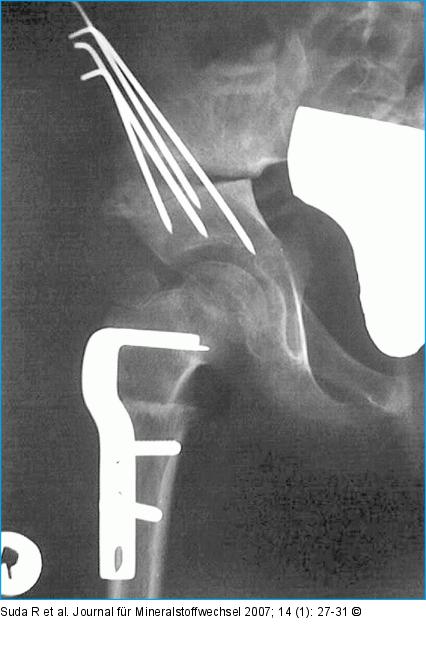

Abbildung 6a-b: Femurosteotomie Zustand nach intertrochantärer varisierender Femurosteotomie mit simultaner Beckenosteotomie nach Salter bei einem 7jährigen Mädchen: (a) postoperatives Röntgenbild, (b) 2 Jahre postoperativ. Der Femurkopf zeigt eine sphärische Ausheilung bei guter Pfannenüberdachung. |

Zustand nach intertrochantärer varisierender Femurosteotomie mit simultaner Beckenosteotomie nach Salter bei einem 7jährigen Mädchen: (a) postoperatives Röntgenbild, (b) 2 Jahre postoperativ. Der Femurkopf zeigt eine sphärische Ausheilung bei guter Pfannenüberdachung. |